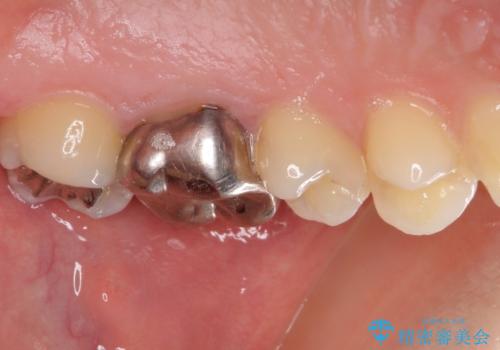

- 奥歯の虫歯と銀歯を気にして来院された患者様です。

セラミックインレーおよびセラミッククラウンによる治療を希望されましたが、虫歯となっている歯は神経近くにまで蝕まれていたため、長期的な予後を鑑みて、PGAインレー(プラチナゴールドインレー)にて修復することとしました。

ゴールドインレーを装着するまでは、金属色が目立ってしまうのではないかと心配されていましたが、表からは見えない位置にあること、銀歯と異なり目立つ色ではないことから、審美的な問題はありませんでした。